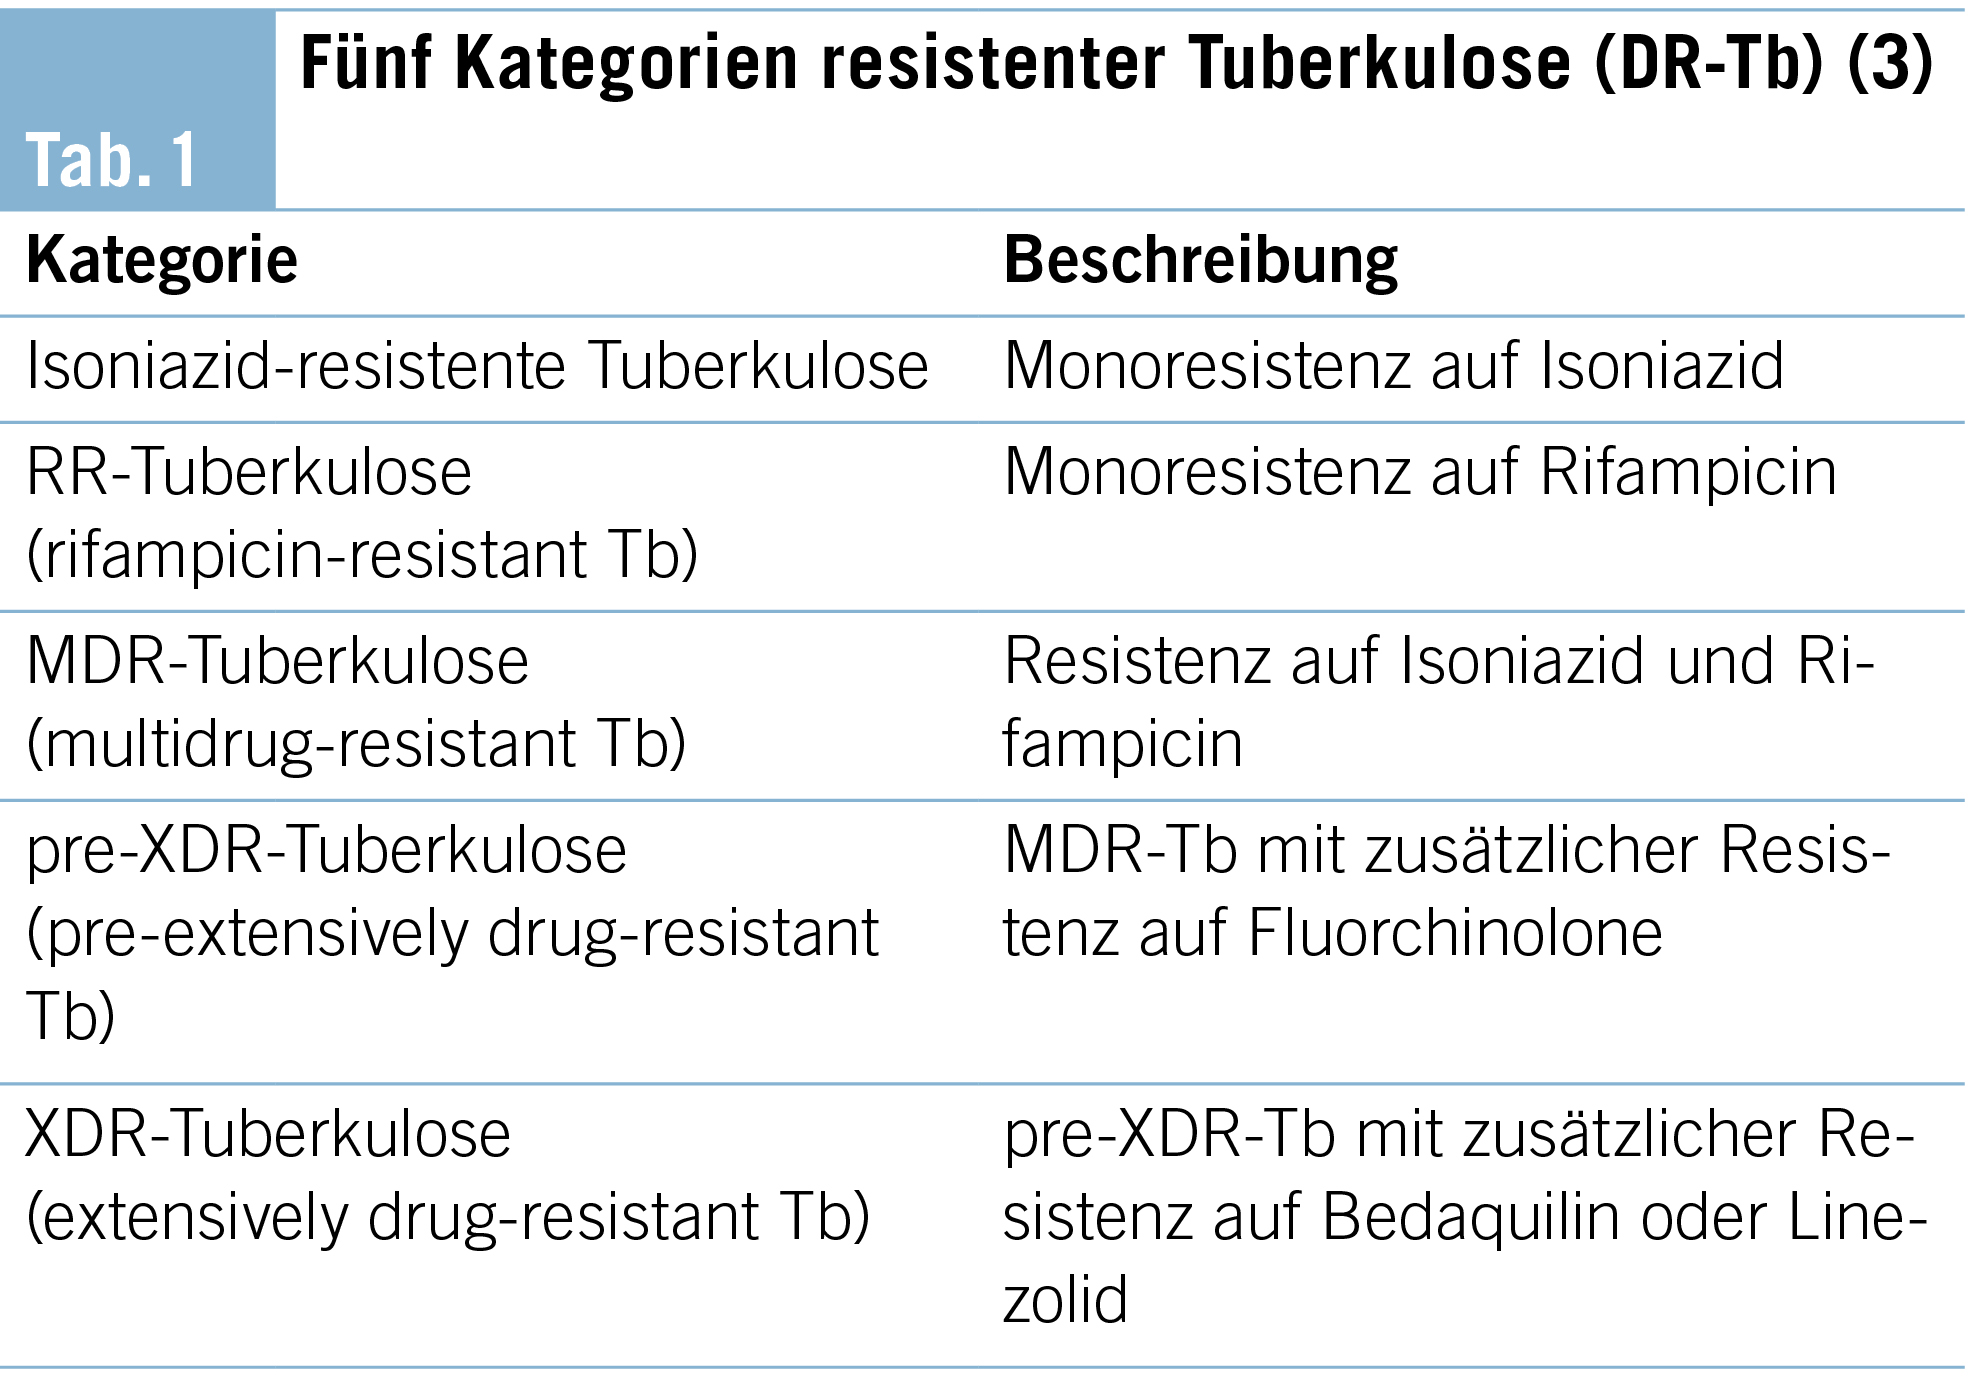

Die resistente Tuberkulose wird von der WHO je nach Grad der Resistenz in fünf Kategorien unterteilt (Tab. 1).